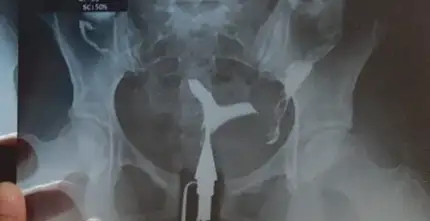

Histereskobi oncesi ve sonrası bu şekilde perde değil bircornis unicollis tanısı aldım doğuştan bu sekildeymis 2 düşüğüm var ne yapacağımı şaşırmış vaziyetteyim tekrar olmakta istemiyorumMerhaba ameliyat olmadım kendi doktorum kavite kötü değil olsa bırakmam dedi ameliyat ederdim üstten hafif basıklık var dedi bende kararsız kaldım bana bıraktı yinede olmadım çünkü doktorlar genelde rahime müdahale çok istemiyorlar bende böyle denemek istedim yeni bıraktım korunmayı bakalım progestanı artıracak birde yatacaksın 3 ay dedi o kadar bazı arkadaşlar sağolsun korkutmaya bayılıyorlar bu konuyu açtığımda bazıları kesin şöyle böyle diye yorum yapmıştı doktormuş gibi neyse bende doktorun dediğini söyledim size içinizi ferah tutun başka doktora görünün isterseniz bi perde mi vardı sizde film varsa atabilir misiniz

Sadece yanlardan mı genişletmişler sanki üstten basık görünüm devam ediyor yine siz bilirsiniz ama başka doktora kesin gösterin böyle doğuran çok insan var yarım rahimle bile varmış çok müdahale ettirmek iyi değil yapışıklık riski çok yüksek bicornis unicollis y rahim diye mi geçiyor acabaHistereskobi oncesi ve sonrası bu şekilde perde değil bircornis unicollis tanısı aldım doğuştan bu sekildeymis

Daha önce özelde tüp bebek merkezine gittim dusuklerimi buna bağlamadı bu sekilde olup üçüz doguran bile var dedi mudahale edilmeyecek dedi sonra ünide doçente gittim laporoskobi yaptı üsten basık seninki dedi müdahale etmedi şimdi bi profa gidiyorum aslında oda ellemek istemedi ama yinede bi histeresmobi yapalim dedi 4 ay önce oldum şimdi rahim filminde biraz daha açsak iyi olur dedi çok az az müdahale ediyoruz o yüzden bu işlemlerde tekrarlama olabiliyor dedi aynı zamanda pcos var bende tedaviyr başlayacaktık artık ama böyle diyince ne yapacağımı şaşırdım doktor doktor gezmeninde pek bir anlamı yok gibi geliyor artık büyük ihtimal bir kez daha gebelik deneyeceğim yine düşük olursa müdahale ettirecegim suanki dusuncem bu yönde evet bu arada bicornis unicollis çift başlı rahim olarak geçiyor y şeklindeSadece yanlardan mı genişletmişler sanki üstten basık görünüm devam ediyor yine siz bilirsiniz ama başka doktora kesin gösterin böyle doğuran çok insan var yarım rahimle bile varmış çok müdahale ettirmek iyi değil yapışıklık riski çok yüksek bicornis unicollis y rahim diye mi geçiyor acaba